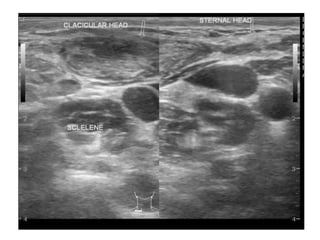

Ultrasound

• Ultrasound is an excellent first-line investigation as it

assess cervical lymphadenopathy and also enables

guided fine needle aspiration cytology.

• The combination of grey-scale imaging and FNAC as a

sensitivity of 92% and specificity 97% in distinguishing

benign from malignant nodal disease.

• Differentiating features from neck metastasis include:

– Nodal matting

– Surrounding soft tissue oedema (less marked than one

would expect given the size of the collections)

– Homogeneity

– Intranodal cystic necrosis and

– Posterior enhancement.

• Doppler examination is particularly useful in

helping distinguish tuberculous infection from

necrotic metastatic disease.

• Reactive nodes (including those in tuberculous

lymphadenitis) demonstrate prominent

vascularity, but mostly confined to the hilum,

whereas malignant nodes demonstrate more

peripheral/capsular vascularity.